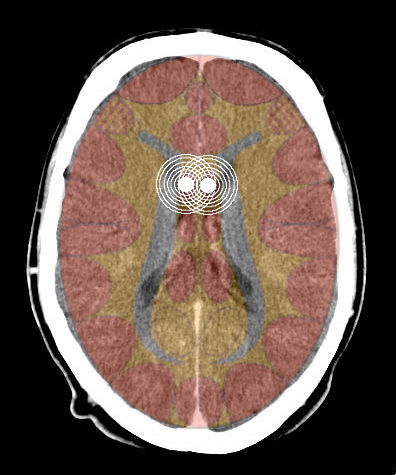

- Requisiti: Si è in costellazione schizofrenica quando due attivazioni colpiscono i due emisferi cerebrali di uno stesso livello:

- le due emiparti del tronco cerebrale;

- i due emisferi cerebellari;

- i due emisferi cerebrali (midollo e/o corteccia).

- Relè cerebrali: Due SBS (uno in ogni emitronco cerebrale);

- Relè cerebrali: Due SBS a livello cerebellare

- Relè cerebrali: Due relè nella sostanza bianca cerebrale;